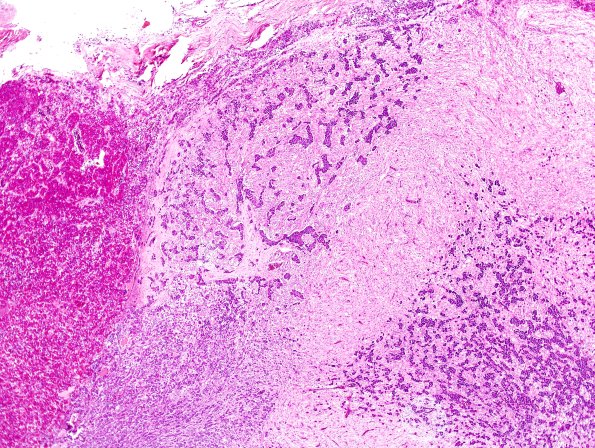

6B2 Pituitary, basophil invasion H&E 1

Increasing magnification of basophil invasion giving second thought as a possible metastasis. (H&E)